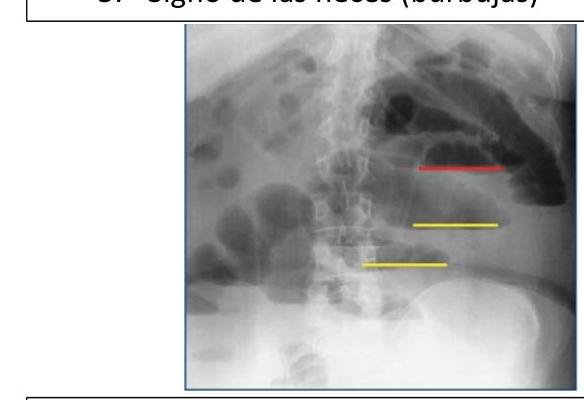

# OCLUSIÓN INTESTINAL ## DEFINICIÓN Se define como la **INTERRUPCIÓN DEL TRÁNSITO INTESTINAL**, lo que impide expulsar gases y heces por el recto. El bloqueo de la luz intestinal se da en su mayoría por factores extrínsecos (adherencias, hernia inguinal, hernia de pared estrangulada) y en pocas ocasiones por obstrucción de la luz. **ADHERENCIAS PERITONEALES**: son bandas fibrosas entre órganos o tejidos o ambos en la cavidad abdominal que normalmente están separados. TIPOS DE ÍLEO | PARALÍTICO / ADINÁMICO | Existe una causa funcional que altera el peristaltismo. La causa más frecuente es la cirugía abdominal (íleo reflejo postquirúrgico). Tras la cirugía, el intestino delgado es el primero en recuperar la movilidad a las 24 horas, seguido del estómago 48 horas, el colon tarda 3 -5 días. | | :--: | :-- | | OBSTRUCTIVO / MECÁNICO | Existe una causa orgánica que lo produce como son las barreras físicas que obstruyen la luz. | | ESPÁSTICO | Hiperactividad descoordinada del intestino que se observa en la intoxicación por metales pesados, porfiria y uremia. Se debe tratar la enfermedad sistémica. | | ÍLEO DE LA OCLUSIÓN VASCULAR | Movilidad descoordinada del intestino isquémico | ## EPIDEMIOLOGÍA - LAS **ADHERENCIAS SON LA CAUSA MÁS COMÚN DE OCLUSIÓN INTESTINAL** - Responsables en 65 - 75 % de los casos (mortalidad de 3.5 - 6%) - El 70% de las adherencias responde a manejo conservador, un 30% requiere manejo quirúrgico. - En el intestino delgado, la obstrucción mecánica es el trastorno quirúrgico más frecuente. ## FACTORES DE RIESGO - Adherencias - **Hernia inguinal** (primera causa en pacientes sin cirugía previa) - **Hernia de pared estrangulada** - Neoplasias - Íleo por cálculo biliar - **Enfermedad de Crohn** - **Vólvulo** - **Intususcepción** - Divertículo de Meckel - **Cuerpo Extraño** # CLÍNICA - **DOLOR ABDOMINAL TIPO CÓLICO** + **NÁUSEA**, **VÓMITO** Y **ESTREÑIMIENTO** - El vómito es más prominente en las obstrucciones proximales - La distensión se asocia al íleon distal. - Los ruidos intestinales son hiperactivos al principio, luego son mínimos | INTESTINO DELGADO | Dolor abdominal, vómitos (fecaloides si es distal), distensión abdominal, hiperperistaltismo con ruidos metálicos | | :--: | :--: | | INTESTINO GRUESO | Dolor y distensión abdominal Vómitos y estreñimiento Incapacidad de expulsar gases y heces | **Obstrucción Estrangulada**: Dolor abdominal desproporcionado, taquicardia, fiebre, leucocitosis y acidosis. ## DIAGNÓSTICO **GOLD STANDARD: RADIOGRAFÍA DE ABDOMEN** (En decúbito y de pie) + Tele de Tórax de pie. ## TRIADA DE RX: - Asas en Intestino delgado dilatadas (+3 cm de diámetro) - Niveles hidroaéreos - Escasez de aire en el colon  Radiografía en decúbito con dilatación de asas de intestino delgado con válvulas conniventes (separado de la base y por el extremo en contacto)  Signo de Collar de Perlas: representa pequeñas cantidades de aire atrapado en las válvulas del intestino delgado, predominantemente lleno de líquido. Se presenta en obstrucción mecánica de ID. DATOS EN **TAC**: 1. Dilatación proximal del intestino 2. Descompresión distal del intestino 3. Contraste luminal que no pasa más allá de la zona de transición 4. Colon con poco gas o líquido 5. Signo de las heces (burbujas)   Signo de **PILAS DE MONEDAS**: Pliegues intestinales engrosados, lisos, rectos y perpendiculares al eje longitudinal de la luz. # TRATAMIENTO ## CONSERVADOR ## SONDA NASOGÁSTRICA / TUBO INTESTINAL LARGO - El 90% de las obstrucciones de ID se resuelven con **SNG y REPOSICIÓN HIDROELECTROLÍTICA** - Debe mantenerse durante 48 - 72 horas. - Si existe obstrucción por estrangulación, obstrucción maligna, hernias encarceladas, cuerpo extraño, enteritis por radiación, peritonitis o abdomen agudo, debe considerarse **cirugía**. ## QUIRÚRGICO Deberá considerarse el manejo invasivo en los siguientes casos: A. **Íleo mecánico intestinal por más de 3 días** B. Drenaje por SNG al tercer día >500 ml C. Edad menor a 40 años o adherencias complejas D. **Obstrucción completa** del intestino delgado (sin aire en intestino grueso) y CPK mayor a 130 Considerar **Cirugía INMEDIATA** en los siguientes casos: - Cirugía dentro de las 6 semanas previas al cuadro de oclusión - Cuadro no resuelto con manejo conservador en las 48-72 horas a pesar de utilizar medio de contraste hidrosoluble por SNG - Presencia de líquido intraperitoneal, edema del mesenterio y signo de las heces en intestino delgado - Dolor abdominal mayor a 4, resistencia abdominal, leucocitos 10,000 o más, PCR 75 mg - Datos de **estrangulación**: fiebre, taquicardia, leucocitosis, acidosis metabólica. ## LAPAROTOMÍA EXPLORADORA 1. La incisión debe permitir tener una adecuada exposición y visibilidad 2. Identificar sitio y causa de obstrucción, si no es obvio, hay que descomprimir el intestino hasta encontrarla 3. Si el intestino está isquémico hay riesgo de ruptura con salida de contenido a cavidad abdominal 4. Después de corregir obstrucción se deben explorar los cuatro cuadrantes. 5. Si es requerido, realizar resección intestinal y anastomosis primaria. ## LAPAROSCOPÍA Solo se realizará en un grupo selecto de pacientes como abordaje - Casos de un primer episodio de oclusión intestinal por **adherencias** - Diámetro intestinal menor a 4 cm . - Sospecha de una banda - Antecedente de 2 o menos laparotomías - Antecedente de apendicectomía o colecistectomía puede someterse a laparoscopía. # ANEXOS